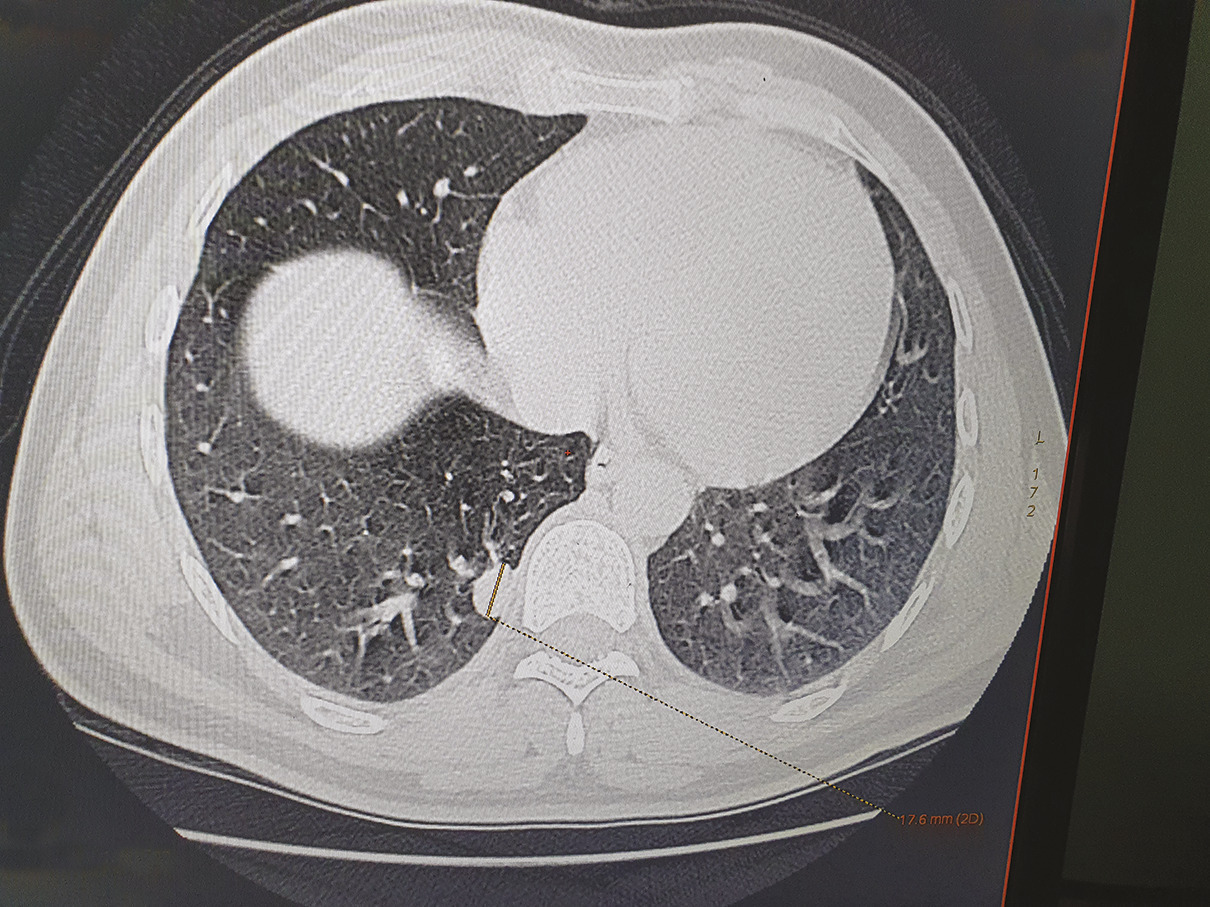

Cet homme de 35 ans, sans antécédents particuliers, avait depuis un mois une toux sèche avec une fièvre, des sueurs nocturnes, une asthénie et un amaigrissement de 10 kg. À l’examen, on notait des conjonctives décolorées, une splénomégalie et des adénopathies sous-mandibulaires. La biologie montrait une pancytopénie, un syndrome inflammatoire biologique, un taux de prothrombine bas (53 %). Sur la tomodensitométrie (TDM) thoracique, on notait un nodule pulmonaire excavé médiobasal droit (fig. 1 ). Des corps de leishmanies intra- et extramacrophagiques étaient trouvés au médullogramme (fig. 2 ). Le patient était traité par antimoniate de méglumine (Glucantime) à raison de 3 g/j pendant vingt jours ; sur la TDM de contrôle cinq mois après la guérison, le nodule pulmonaire s’était densifié (fig. 3 ).

L’atteinte pulmonaire dans la leishmaniose viscérale est considérée comme rare. Cependant, une toux sèche persistante est une caractéristique négligée, mais assez courante puisqu’elle est notée chez près de 83 % des patients.1 Cette atteinte est souvent rapportée chez les immunodéprimés, en particulier ceux infectés par le VIH.2 L’immunité protectrice contre la leishmaniose viscérale dépend de cytokines pro-inflammatoires comme le TNF-alpha, l’interleukine 12, et l’interféron gamma ; lorsqu’ils sont à un niveau bas, une formation de granulomes désorganisés est induite.3 Le diagnostic de leishmaniose viscérale doit être évoqué en présence d’un nodule pulmonaire solitaire même chez les sujets immunocompétents pour une prise en charge rapide.